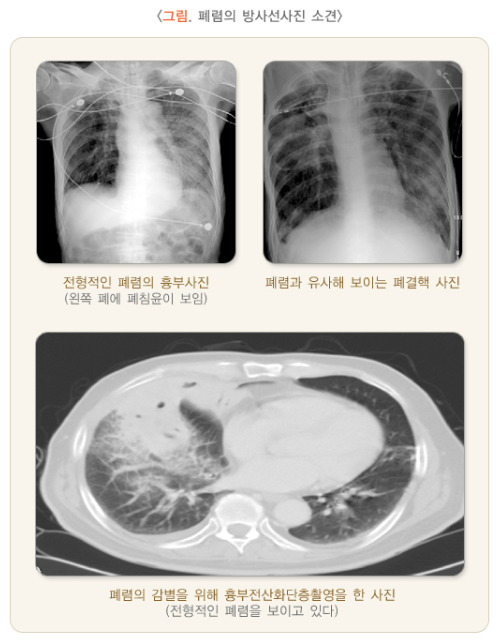

급성 폐렴은 급격히 진행되는 호흡기 질환으로, 치료가 지연되면 사망에 이를 수 있는 위험한 질병입니다.